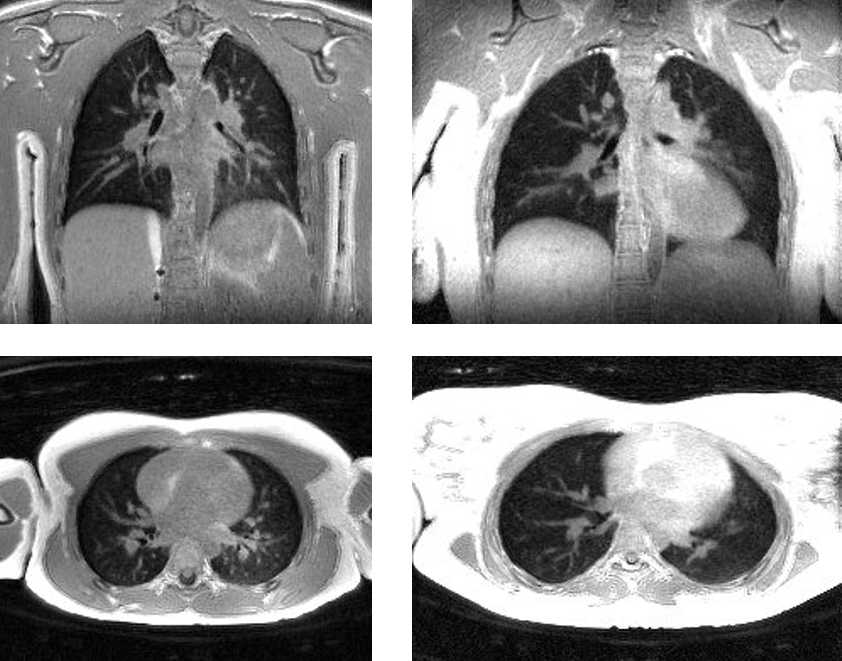

We work on a range of projects, taking on new ones opportunistically, and projects currently include Metabolic MRI with hyperpolarized contrast agents, Simultaneous PET/MR imaging systems, Lung MRI, Myelin MRI, Radiation treatment planning, and Prostate and kidney cancer prediction based on historical imaging data.